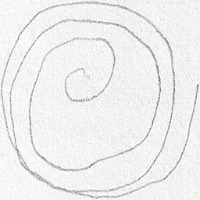

Parkinson's Disease Early Detection: This model can be used in telemedicine and eHealth applications to analyze drawings or handwriting samples drawn by patients. Early diagnosis of Parkinson's Disease can help in beginning the treatment early and slow down the progression of the disease.

Medical Research: Researchers studying Parkinson’s Disease can use this model to analyze large sets of drawings or handwritings, identifying trends and correlations between identified Parkinson’s Disease positive cases and the characteristics of their drawing.

Home Monitoring System: This model can be incorporated into a home monitoring system where elderly individuals or at-risk populations can regularly submit handwriting or drawing samples. These can be analyzed for Parkinson's symptoms, enabling early intervention and care.

Rehabilitation: For those patients already diagnosed with Parkinson's Disease, this model can help monitor the progression of their disease based on regular analysis of their handwriting or drawings. This would facilitate tailoring their treatment and rehabilitation program based on their current status.

Pharmaceutical Industry: Drug companies can use this model in clinical trials to monitor the impact of new Parkinson's Disease drugs on patients. This can provide valuable data on the effectiveness of the drugs, based on whether they help improve the drawing and handwriting symptoms associated with Parkinson's.